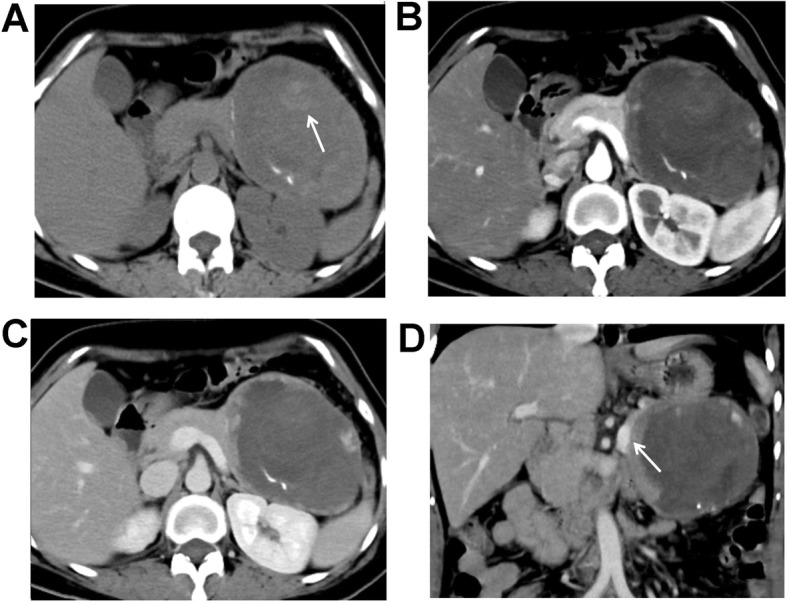

Fig. 3.

A 50-year-old female patient with pain in the upper abdomen. Plain CT scanning + enhanced scanning showed pseudo-papillary neoplasm of pancreas (SPNP). a Plain scanning showed a huge oval cystic and solid mass at the pancreatic tail, of which the boundaries were clear. Punctate calcifications were found around the mass. Small patchy bleeding focuses were found in the mass (white arrow). b Low enhancement of the lesion was found in the arterial phase, which was lower than the normal pancreas, and showed “ball-holding” changes with the pancreatic body. c Persistent enhancement of the solid components was found in the portal venous phase, which showed “floating cloud” sign. d Reconstructed coronal image showed compressing and circuity of the splenic vein (white arrow)